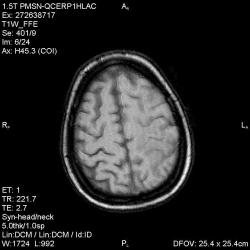

Из анамнеза - Женщина 45 лет. За год похудела на 15 кг (со слов матери), в последние месяцы случались эпизоды потери сознания. Онкозаболеваний и прочая в анамнезе нет. Сознание спутанное, из особенностей в анализах только подъем амилазы крови.

К сожалению, не владею методом КТ, но учитывая наличие неравномерного уплотнения в мозговых структурах с элементами очаговых "вкраплений", единственное, что приходит на ум - это рассеяный склероз. Хотелось бы уточнить, что беспокоило пациентку в течение последнего года кроме потери веса и эпизодов потери сознания? Была ли какая-либо очаговая неврологическая симптоматика? Отмечались ли какие-либо расстройства в двигательной или чувствительной сфере и т.д.? С уважением Helenmar.

И это точно не РС, т.к. характер очагов другой, ни один из них не копит контраст, нет субтенториальных очагов (извиняюсь, я этого в сообщении не указал), нет клиники.

"Раскрою" карты. Мы подумали о синдроме MELAS (mitochondrial encephalomyopathy, lactic acidosis and stroke) - дословно, митохондриальная энцефаломиелопатия, лактоацидоз и инсульт. В качестве дифференциальной диагностики можно было бы предположить вирусный энцефалит, но опять-таки, расположение очагов смущает - только с одной стороны и в абсолютно различных структурах.

В данном случае мы видим импульную последовательность FLAIR - режим с подавлением сигнала от воды, поэтому ликвор гипоинтенсивен, а также (вторая серия) - изображения, взвешенные по T1 после введения контрастного препарата. На T1 жидкость (ликвор) также представляется гипоинтенсивной. Зато на этих сериях гиперинтенсивны сосуды, т.к. контрастное вещество циркулирует в кровяном русле.

Изменения носят сосудистый характер. Процесс достаточно острый, имеется объемное воздействие, борозды левой гемисферы компремированы. По поводу MELAS синдрома очень сомневаюсь, почему поражена только левая гемисфера? Надо делать МР-ангиографию, смотреть нет ли стеноза

MELAS синдром - дебютирует с детских лет, характерен целый комплекс неврологических проявлений, заболевание генетическое, поражение системное, хотя есть множество вариантов митохондриального поражения, все же сомнительно. Хотелось бы акцентировать внимание, что гиперинтенсивные очаги есть в мозолистом теле, поражены выражено перивентрикулярные отделы, U -пути, белое вещество, поэтому так категорично демиелинизацию не вычеркивала бы из дифряда ( хотя тоже нетипично односторонее поражение). Думаю, для объективных выводов все же мало общей информации о пациентке, были ли клинические эпизоды раньше, чем объяснить такую потерю веса (возможно есть проявление паранеопластического синдрома?). Ну и МРТ-контроль в динамике, ангиография.

Да, неоднозначный случай. Точно не РС и не ОНМК. Я бы написала асимметричную лейкоэнцефалопатию неясного генеза. Можно было бы думать о лимфоме (полифокальное поражение, да еще мозолистое тело вроде бы задействовано (эх, сагиттальчики бы)). Но! Учитывая отсутствие накопления КВ.... Ну и надо исключать интоксикацию, всяческие аутоиммунные процессы (в т.ч. и васкулиты), сахарный диабет, ну и естественно наследственную патологию обменных процессов. УУУх! Вот.......

Имхо ишемический онмк в бассейне сма. Особенно показательны 5-й и 6-й файлы, отграничение как раз на границе бассейнов средней и перикаллёзной. Плюс одностороннее поражение.